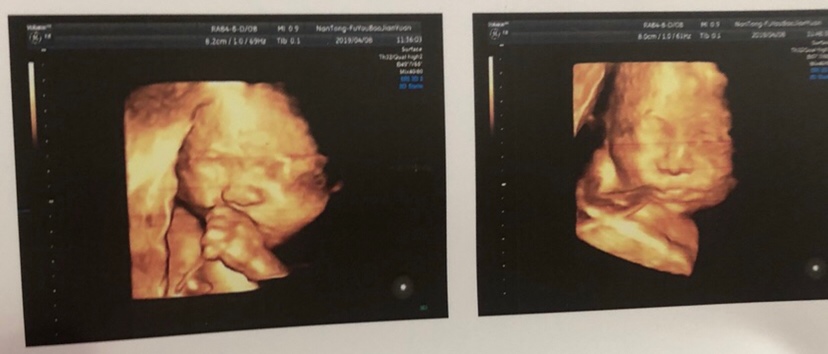

孕26周+2天

哈哈哈,我们的也在吃手手

林巧灵:哈哈哈,好可爱!接四维顺利通过!